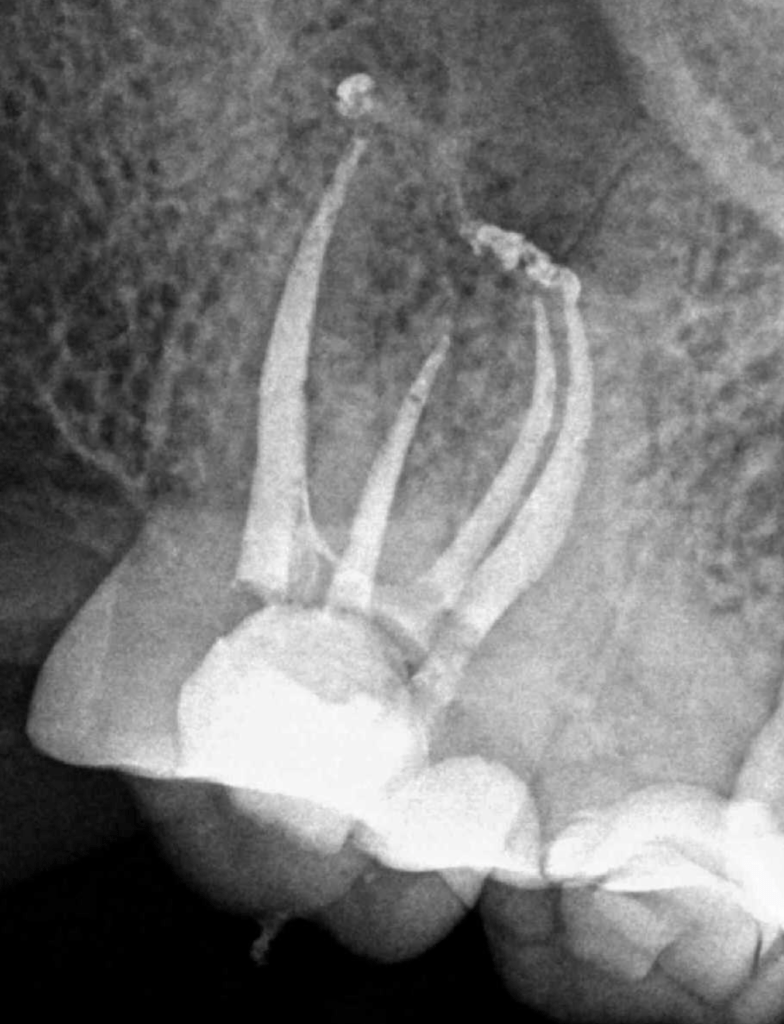

Casos de anatomia compleja

Molar gran curvatura bifurcación palatino